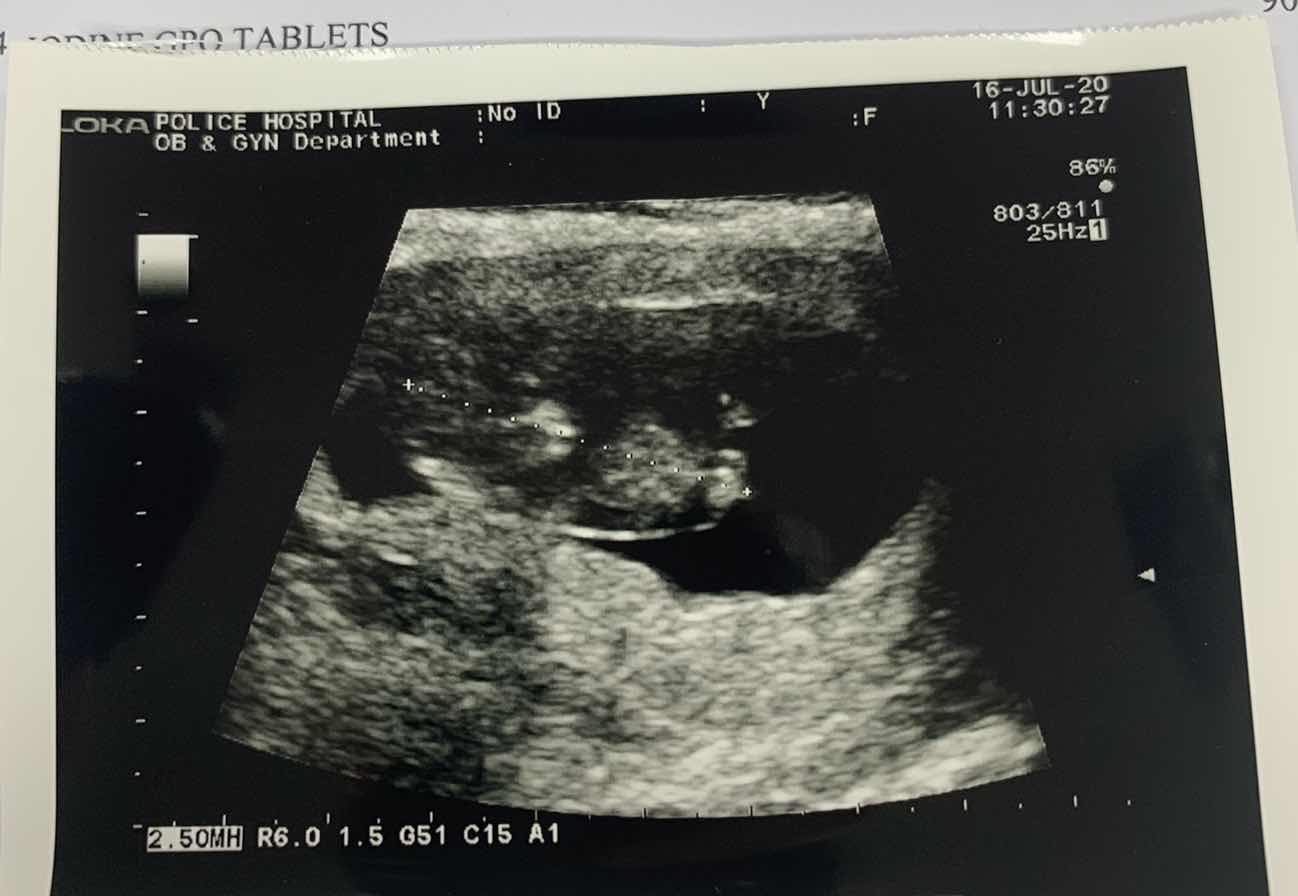

10w3dคะ ตัวนิดเดียว

ซาวด์ตอน13/w คะ